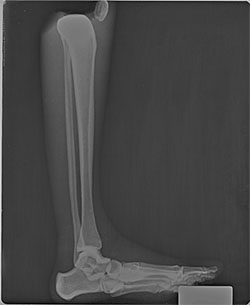

BREAK-APART PIXY Hands X-Ray BREAK-APART PIXY Legs X-Ray 1 BREAK-APART PIXY Legs X-Ray 2 BREAK-APART PIXY Torso X-Ray